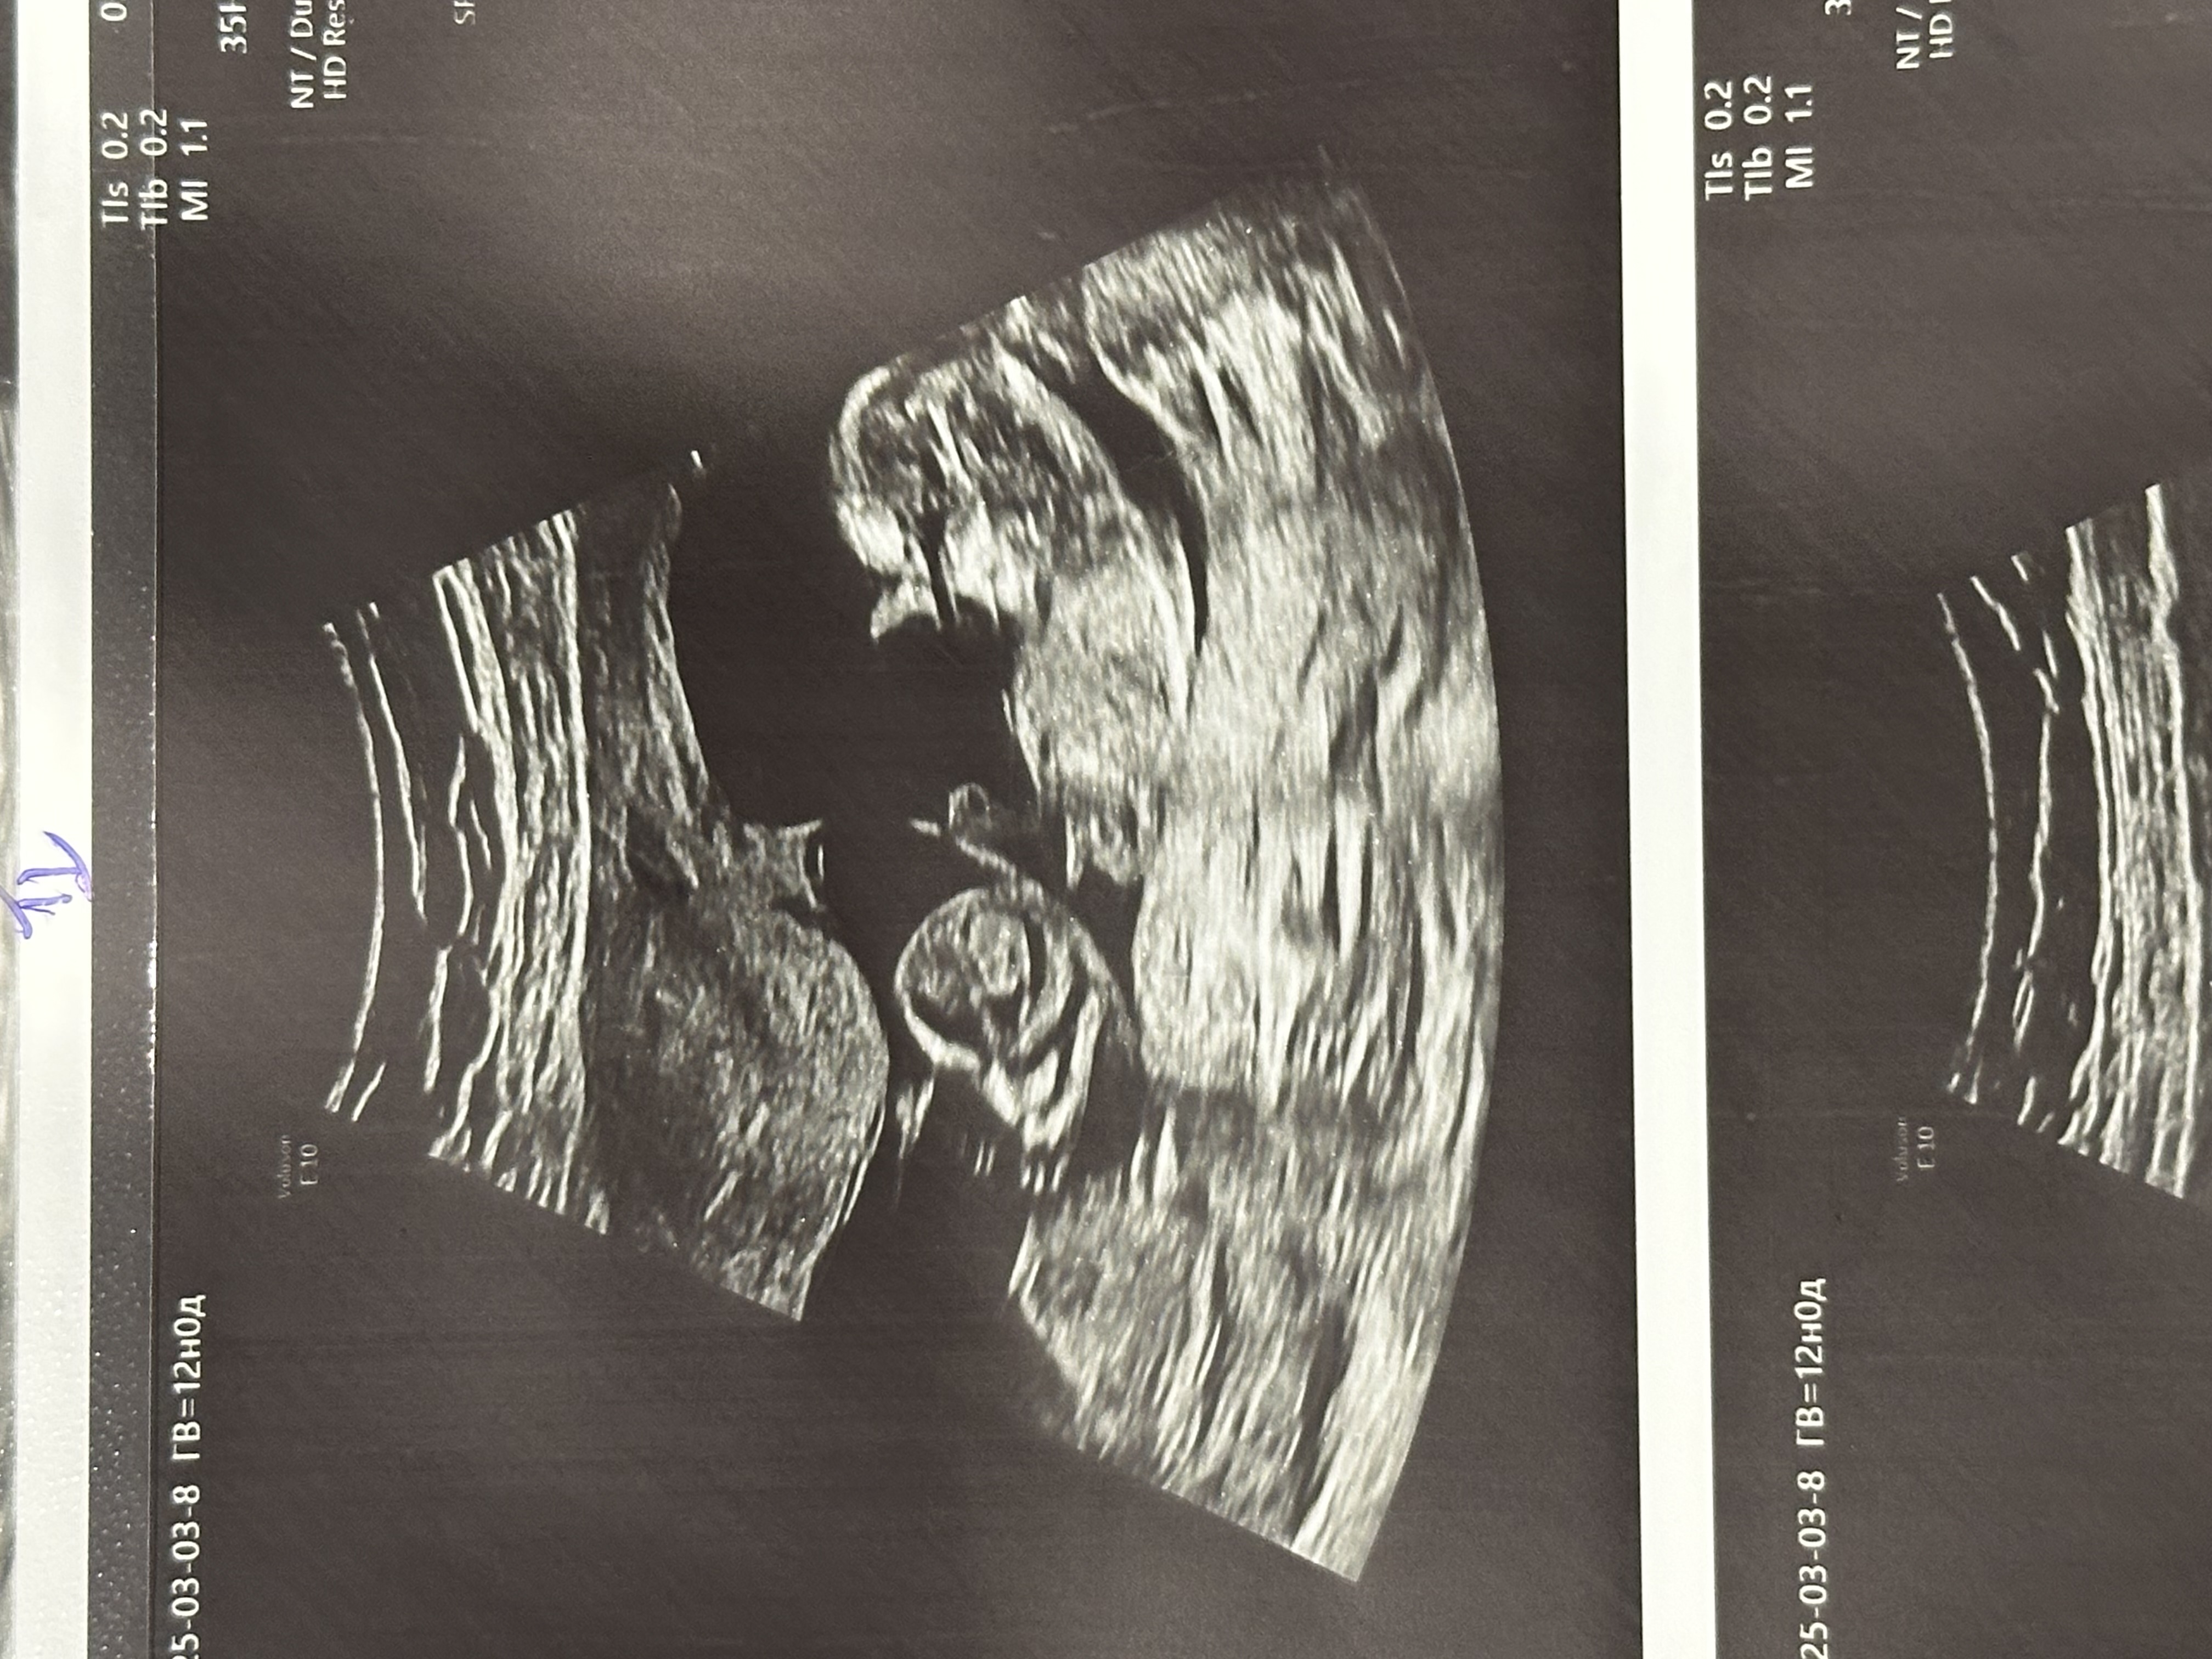

Первый скрининг Ди-ди двойня

Сегодня были на первом скрининге, все посмотрели, жильцы, как сказала врач, в плацкарте😂 смешные, срок поставили одному 12+3, другому 12+5, хотя я думала сегодня ровно 12. Первый низковато прикрепился, очень надеюсь, что уже повыше будет на следующем узи… первый по задней стенке, второй по передней. Предположили мальчишку и девчонку🥹 сдала нипт и кровь, но в целом моя душенька спокойна пока, очень радостно🥰